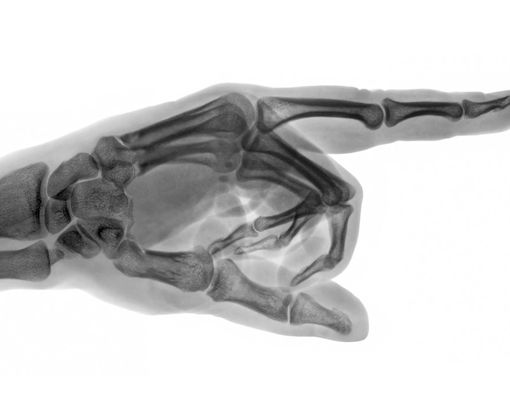

Menurut dr. Devia Irine Putri, untuk mengetahui atau mendiagnosis jenis kanker tulang, ada beberapa tahapan yang perlu dilakukan oleh dokter.

“Selain dari wawancara medis dan pemeriksaan fisik, biasanya akan didukung dengan pemeriksaan lain, seperti tes pencitraan, rontgen, CT scan, MRI dan juga melakukan biopsi,” jelas dr. Devia.